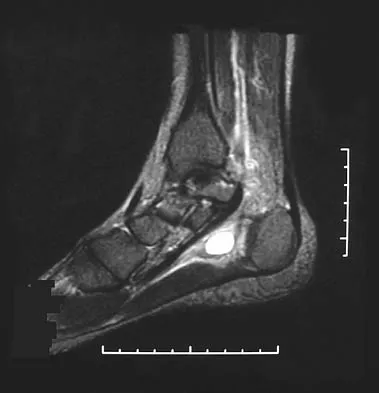

Master AAOS & ABOS boards with 2026 practice MCQs (Set 1), covering shoulder instability, rotator cuff pathol…

Master AAOS & ABOS with practice MCQs for Set 1, covering complex spine disorders, sports medicine injuries, …